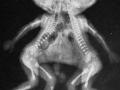

Conjoined twins delivered at home, family seeks help - Hindi News | Conjoined twins delivered at home, family seeks help | Latest health News at Lokmattimes.com

Health :Conjoined twins delivered at home, family seeks help

Lakhimpur Kheri (UP), Oct 5 A Dalit family in Lakhimpur Kheri has appealed for financial assistance from the ... ...